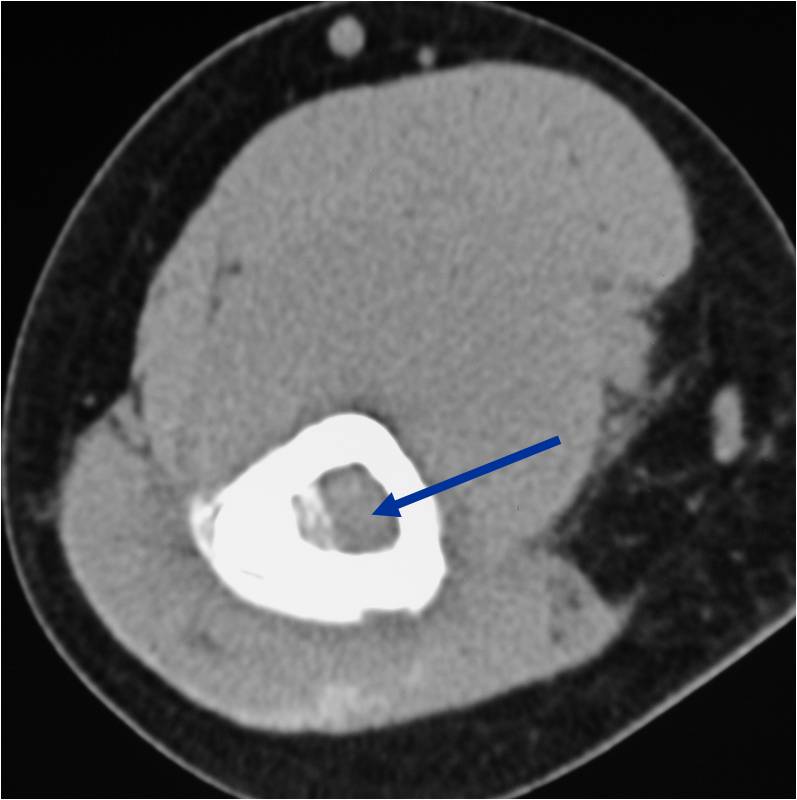

- Soft tissue mass— by CT (80%); by MRI (100%)

- Sequestra (16%)